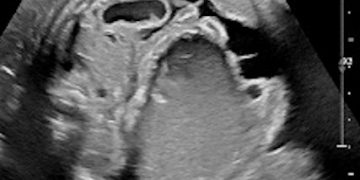

Caso del Mese di Dicembre 2021

Cari soci, finalmente la soluzione del caso del mese di Dicembre! Scarica il File L'attesa è finita: Al seguente link la...